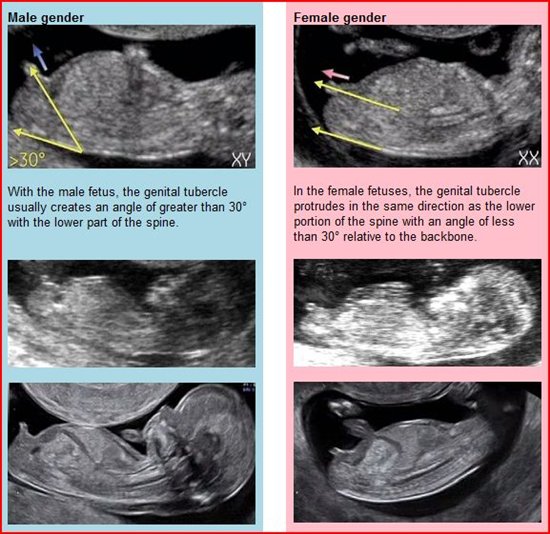

I'm not sure I can see the nub but I'm guessing cowboy :-)

I am still thinking it just resembles this girl nub here Attachment 22059

Leaning girl

It could be 50/50 at this time. Baby is also mid roll over so the guess wouldn't be accurate. Have any other shots?